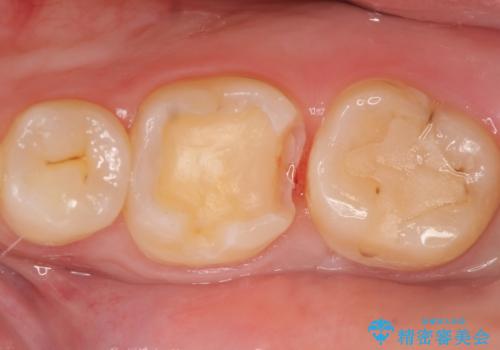

- 冷たいものを飲むと、左下奥歯がしみると来院された方の症例です。

検査の結果左下6が虫歯になっていたため、セラミックインレーによる修復を行いました。